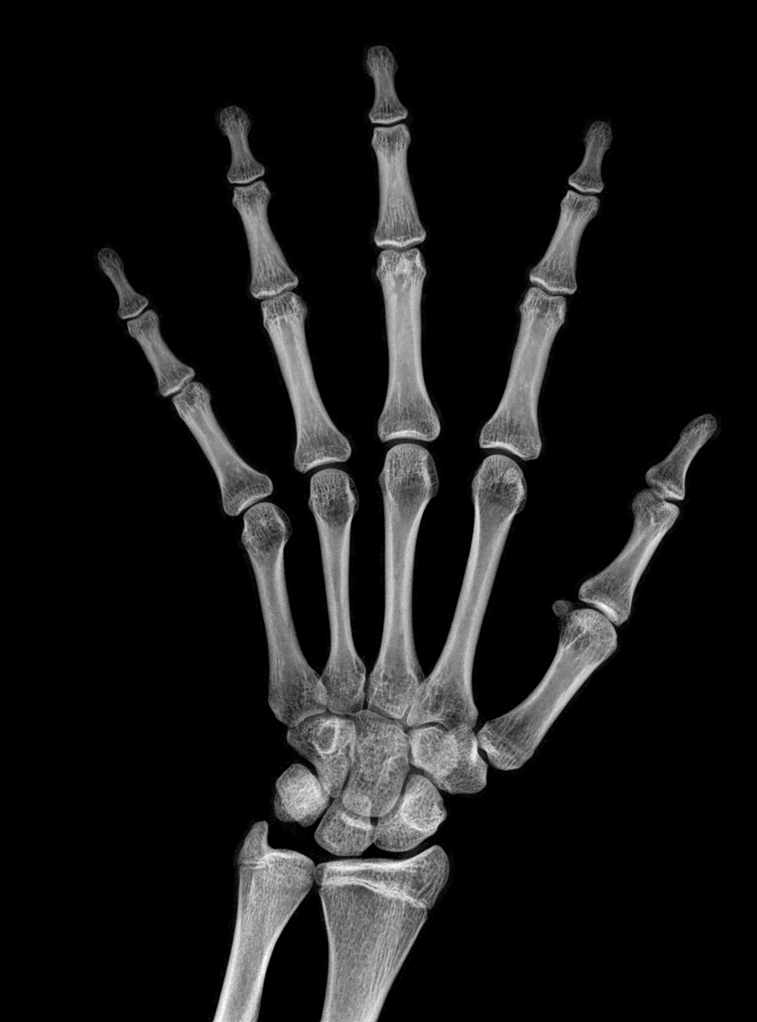

Refer to caption

(a) resolution 2044×1514204415142044\times 1514, run time 0.35s, α=1.34𝛼1.34\alpha=1.34

(b) resolution 2044×1514204415142044\times 1514, run time 0.35s, α=1.39𝛼1.39\alpha=1.39

(c) resolution 2044×1514204415142044\times 1514, run time 0.35s, α=1.63𝛼1.63\alpha=1.63

(d) resolution 2044×1514204415142044\times 1514, run time 0.35s, α=2.42𝛼2.42\alpha=2.42

(e) resolution 2044×1514204415142044\times 1514, run time 0.35s, α=2.31𝛼2.31\alpha=2.31

(f) resolution 2044×1514204415142044\times 1514, run time 0.35s, α=3.61𝛼3.61\alpha=3.61

(g) resolution 2044×1514204415142044\times 1514, run time 0.35s, α=3.02𝛼3.02\alpha=3.02

(h) resolution 2044×1514204415142044\times 1514, run time 0.35s, α=1.47𝛼1.47\alpha=1.47

(i) resolution 2044×1514204415142044\times 1514, run time 0.35s, α=2.11𝛼2.11\alpha=2.11

(j) resolution 2570×2040257020402570\times 2040, run time 0.58s, α=2.34𝛼2.34\alpha=2.34

Figure 10: From left to right in each panel: input X-ray images (left), our estimated soft tissue (middle) and estimated bone image (right). The resolution, running time of our algorithm and parameter α𝛼\alpha are provided. For these practical images, our method requires about half second to achieve the bone and soft tissue decomposition task in MATLAB language on a laptop. Higher performance can be achieved by C++ language on a better hardware.

In the third experiment, we applied our method on a hand X-ray image data set (RSNA), which contains more than 10,000 hand X-ray images. And the image has high resolution (usually larger than 1514×2044151420441514\times 2044). These images are collected from clinical applications. Therefore, we can apply our method on these practical images, showing the efficiency and effectiveness of our method on real high resolution images.

In each panel of Fig. 10, the input image (left) is decomposed into soft tissue (middle) and bone image (right) by our method. Although we only show the first ten images from the data set, the results for the rest images are similar.

The bone images have better image contrast since the parameter α1𝛼1\alpha\geq 1 is theoretically guaranteed. Such enhancement can also be directly told by radiologists. Such enhancement is good for bone diagnosis in practical applications.

Moreover, the running time of our method on such high resolution images is less than half second in the MATLAB language on a laptop. Therefore, it can achieve higher performance on a better hardware in real applications. If higher performance is required, our model can be solved by the parallel Laplace equation solver on a modern graphic process unit (GPU), which usually has thousands of cores.